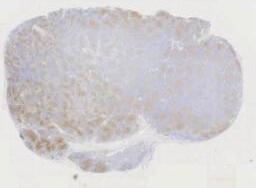

第五例 “一例少见的淋巴结病变” 男/66岁,左颈部淋巴结。

临床资料:   男,66岁,主诉:水肿、颈部淋巴结肿大,同期发现房颤。现病史:2020-05出现心悸伴颜面部、颈部、四肢水肿,尿量减少(约500ml/d),咳嗽、喘憋、活动耐量明显下降。外院完善ECG:“房颤”,颈部超声:双侧颈部淋巴结肿大。2020-06我院查:血常规:(-),肝肾功:LD365U/L,余(-);心肌酶(-);NT-proBNP1465pg/ml;感染:HBcAb(+),HBsAb(+);ECHO:LVEF69%,左房增大,心包少量积液。PET-CT示:1.左侧颈部(IV区、V区)、左侧锁骨上下、右肺门及后纵隔、腹膜后、肠系膜上多发代谢增高淋巴结(大小约0.5-1.6cm,SUVamx13.2),右心房、右心室及双侧心耳见多发代谢增高结节和肿物(大小约2.0×2.3-5.8×7.6cm,SUVamx24.6)、第2/3组小肠壁明显增厚且代谢增高异常(SUVamx17.1)。取左颈根部淋巴结送检。

大体所见:   淋巴结样组织数枚,直径0.5-2cm。